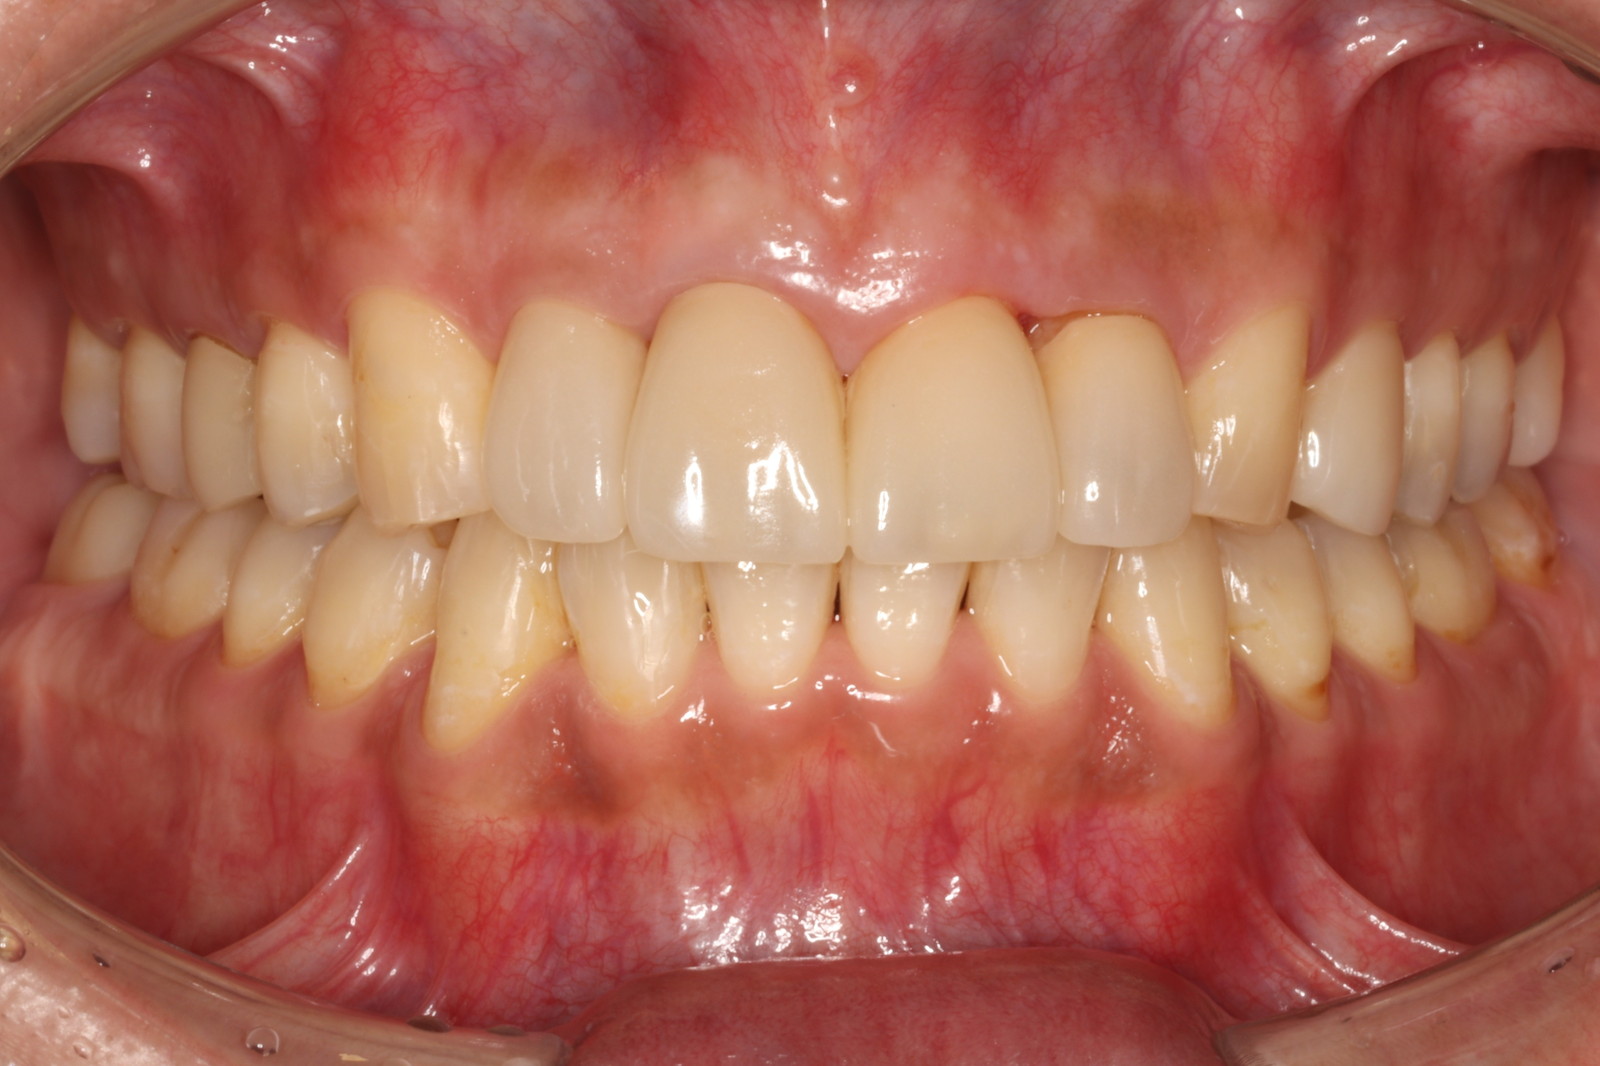

当院では、これらを組み合わせた「セラミック矯正」を提供しています。具体的には、セラミックの被せ物を使って歯の形や色を整えながら、同時に歯並びも改善していきます。

比較表から分かるように、セラミック矯正は短期間で美しい歯になるというメリットがあります。

しかし、その一方で「健康な歯を削る」必要があります。セラミックの被せ物を装着するためには、どうしても天然歯を削らなければなりません。

そのため、健康な歯を削ることに抵抗がある方には、この治療法は不向きかもしれません。そのような方には、矯正治療をおすすめします。矯正治療についての詳細は、矯正治療のページをご覧ください。